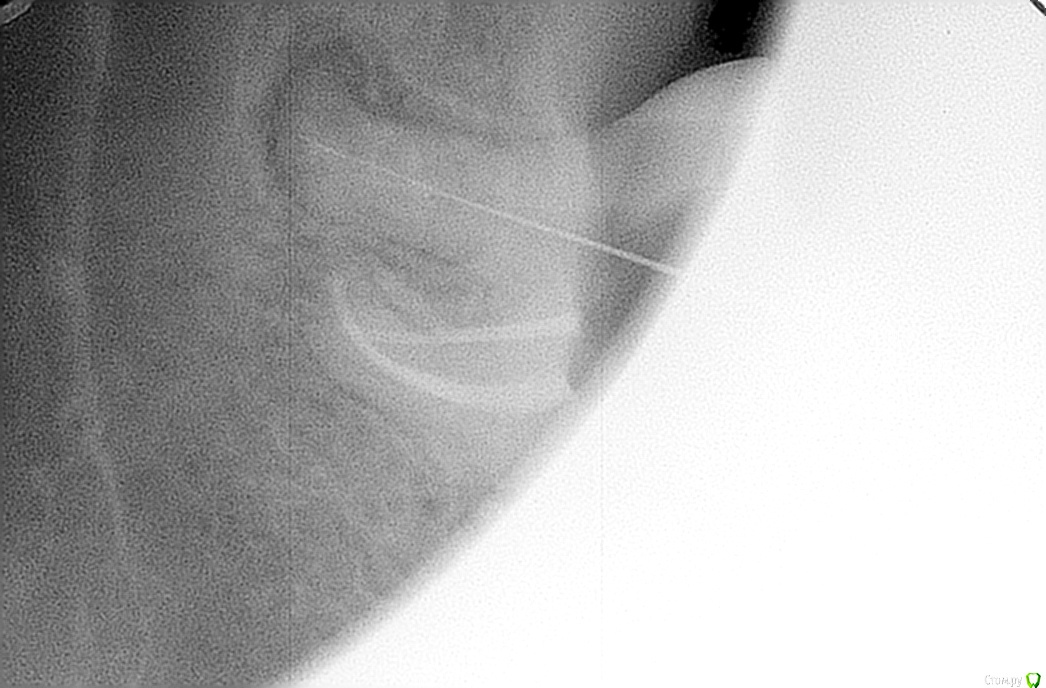

y2006 Опубликовано 28 сентября, 2015 Автор Поделиться Опубликовано 28 сентября, 2015 (изменено) панорамы нет - есть этапы лечения -разница по времени неделя (первый с иглой, второй с "заполненной" гранулемой)посмотреть бы панорамный снимок (ОПТГ) Изменено 28 сентября, 2015 пользователем y2006 Ссылка на комментарий

y2006 Опубликовано 28 сентября, 2015 Автор Поделиться Опубликовано 28 сентября, 2015 "дорог" ,если можно так выразиться.но на данный момент времени идет речь о пломбе со штифтом, как и было до появления гранулемы, не о коронке... сегодня снова уложили лекарство , чтобы через неделю запломбировать окончательно. скажите, а выход препарата в полость гранулемы это нормально (фото 2)Если этот зуб Вам "дорог" и Вы готовы тратить на него время и деньги... а именно протезировать зуб вкладкой и коронкой, то можно еще по бодаться. Ссылка на комментарий